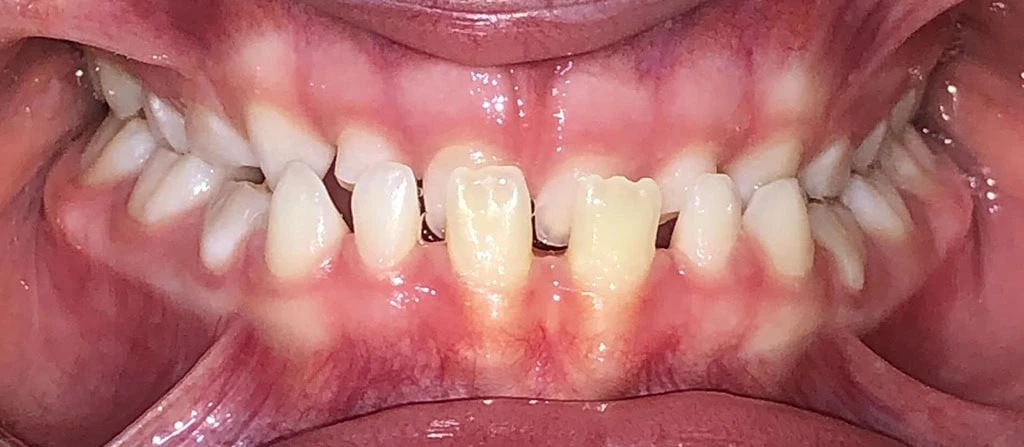

Actual Patient: Bailey

Img Before 3 1 Img After 3 1

Severe “Overbite”, BUCK TEETH, Narrow Jaws, Severe Deep Bite

Bailey Before 1 Beliy after img

7.5 months

Front View

Top View

Right & Left Sides